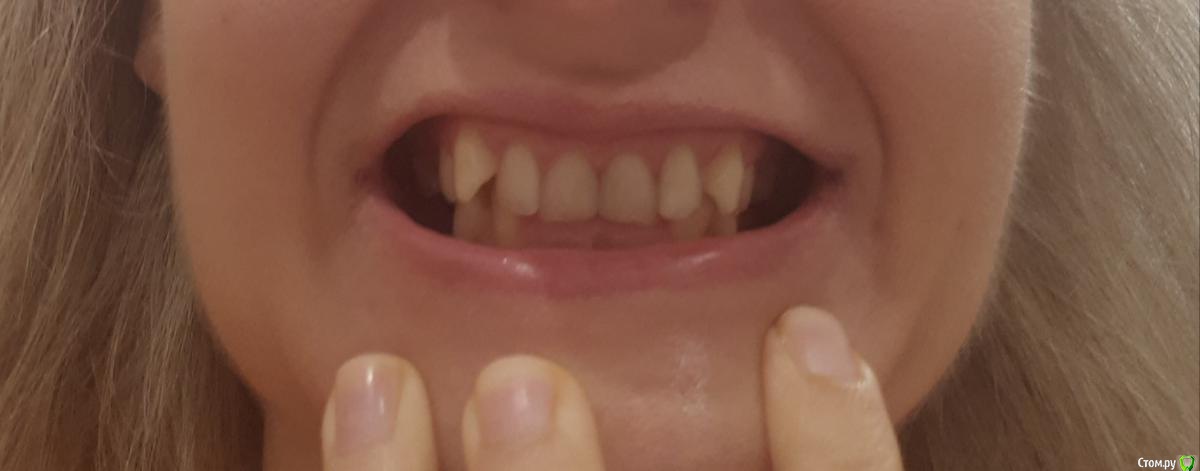

Thunder Опубликовано 17 октября, 2019 Поделиться Опубликовано 17 октября, 2019 Приветствую всехПрошу быть снисходительными: рассказываю свою историю первый раз, заранее приношу извинения за возможный сумбур и некорректность в использовании проф. терминологии. Мне 40 лет. У меня:-глубокий прикус-скученность зубов во фронтальном отделе в/ч и н/ч; -короткая уздечка верхней губы, -мелкое преддверие полости рта, -тонкий биотип пародонта; -проблемы с суставом (левым), который периодически дает о себе знать: обычно ограничивается щелканьем, но пару раз и воспалялся (боли, рот с трудом открывался, особенно по утрам). Ничего, кроме местных мазей на сустав не наносила и особенно им никогда не занималась.- В этом году мне поставили диагноз полиостеоартроз (болят суставы нижних конечностей). - постепенно появился перекос челюсти влево, видно уже невооруженным глазом (возможно, после удаления верхней левой восьмерки)Прикус никогда не исправляла, по разным причинам, в том числе, потому что не хотела ставить брекеты. И сейчас не хочу (комплексы). Комплексы от некрасивой улыбки тоже были, но к своей внешности за столько лет уже привыкла (и смирилась), кроме того она мне совершенно не мешала жить. Однако!В последние годы вынесла основную мысль от стоматологов – мои суставы разрушаются (в большей степени левый), происходит это из-за моего прикуса, который срочно надо исправлять. Эстетика лица для меня – вторична. Вся работа над зубами должна проводиться именно для сохранения сустава (ну и чтобы зубы не потерять).В начале 2019 г. были сделаны ОПТГ, КТ и ТРГ. Есть еще зонография ВНЧС (правда от 2017г.) // не поняла, как КТ подгрузить, но есть описание врача Пикассо. Если надо будет, просто загружу как текст. Остальные фото, надеюсь, подгрузить получится// По КТ ортодонт, к которому я, наконец, обратилась, выявил «убыль костной ткани межальвеолярных гребней и вестибулооральных стенок по смешаному типу до 2,0 мм.» (кортикальная пластинка истончена по вестибулярной поверхности на передних зубах (в/ч зубы 1.2-1.1,2.1-2.4; н/ч зубы 3.1.-3.4, 4.1-4.5) до 0,1 мм). Мой ортодонт (лечение на капах) сказала, что риск потерять зубы при лечении на капах – 50/50, при лечении на брекетах – и того выше. После этого, конечно, я ушла.Стала искать дальше. Каждый раз мнения разнились:1 вариант: можно капами исправить прикус, но крайне осторожно2 вариант: только (!) брекеты. Тема потери зубов обходится стороной или уверяют, чтобы зубы останутся на месте засчет длинных корней. Если я не поставлю брекеты притом срочно – через несколько лет я потеряю все зубы, и мне придется тратиться на съемные протезы3 вариант: зубы вообще не трогать, просто всю жизнь носить каппу, помогающую моему суставу.4 вариант (стоит особняком): суставная каппа на нижнюю челюсть + одновременно аппарат ALF на верхнюю.Почему ALF? потому что из всех ортодонтических аппаратов для исправления прикуса этот – самый щадящий. Брекеты категорически не рекомендованы, потому что самые агрессивные по воздействию, каппы дороже + отмели из-за сустава: его было удобнее лечить параллельно с ALF. Смысл использования у меня ALF (как поняла) не столько в расширении челюсти, сколь в изменении наклона верхних зубов, которые не «пускают» нижнюю челюсть вперед. Мои зубы при этом не выпадут, а врастут в кость, изменив угол наклона.Второй этап – ALF или инвизилайн на нижнюю челюсть; и для возобновления смыкания боковых зубов – пломбы или коронки (эта часть смутила). В данном лечебном плане было прекрасно все, кроме моей неуверенности в достаточной квалификации врача. У меня сложилось впечатление, что для врача эта методика как бы.. далеко не основная. Она использует ALF просто как один из вариантов ортодонтических аппаратов (наряду с брекетами и пр.), а я так понимаю, у ALF философия немного другая (тесная связь с осанкой, остеопатией и пр.) – хотя могу и ошибаться. И в принципе эта методика новая, не особенно опробованная в России, отзывов нет, особенного опыта у врачей тоже. Страшно.Мучают вопросы, на которые здесь, возможно, получу ответы:1. мне были рекомендованы френулопластика на в/ч, вестибулопластика на н/ч. На сколько это необходимо в моем случае и что будет, если я их делать не буду2. последний ортодонт мне пригрозил полной потерей зубов через некоторое время, если не поставлю брекеты. Она была единственной, кто мне озвучил подобные последствия. Альтернативой исправления прикуса действительно будет только полное протезирование через несколько лет? если я не буду делать ничего, то чем, на самом деле это грозит? 3. какие ортодонтические аппараты при моих лежащих на поверхности зубах мне рекомендованы? не потеряю ли я зубы в результате лечения?страшно! 4. ваше мнение об ALF!5. в продолжение 3-го вопроса: возможно ли (при варианте «брекеты») мое лечение на лингвальных брекетах? можно в комбинированном варианте: в/ч лингвальные + н/ч обычные вестибулярные? готова терпеть все неудобства с ними связанные. но "внешние" брекеты не хочу, не могу психологически заставить себя носить. 6. так понимаю, что, учитывая мой диагноз полиостеоартроз и проблемы с суставом – о нем я тоже не должна забывать. И должна лечиться у врача, который эти проблемы (и все остальные) умеет учитывать. В общем, хотелось бы услышать ваши рекомендации по поводу врача в Москве. Можно в личку Заранее спасибо! Ссылка на комментарий

krokomot Опубликовано 17 октября, 2019 Поделиться Опубликовано 17 октября, 2019 сделайте фото передних зубов с десной со вспышкой, попросите кого-нибудь. зубы вы точно не потеряете, но проблемы есть. Ссылка на комментарий

krokomot Опубликовано 21 октября, 2019 Поделиться Опубликовано 21 октября, 2019 Не вижу проблем использовать бреккеты. Атрофии десны нет. Ставте бреккеты и лечите свой прикус. Ссылка на комментарий